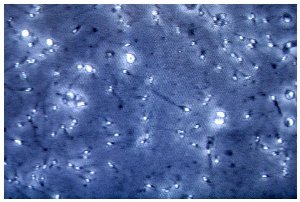

I ricercatori hanno esaminato sei campioni di liquido seminale provenienti da uomini sani, con parametri nella norma. In tutti i casi sono state rilevate particelle plastiche con dimensioni comprese tra circa 2 e 13 micrometri. Si tratta di grandezze molto ridotte: la testa di uno spermatozoo misura in media tra 5 e 8 micrometri.

La concentrazione media rilevata è di circa 50 particelle per millilitro. Il valore è basso rispetto al numero di cellule presenti nel liquido seminale, ma indica comunque una presenza costante. Ordini di grandezza simili sono stati osservati anche in altri fluidi biologici umani, come sangue, placenta e latte materno.

Le particelle risultano disperse nel plasma seminale e non aderiscono agli spermatozoi né penetrano al loro interno. Non è stato osservato un contatto diretto con le cellule germinali nei campioni analizzati.